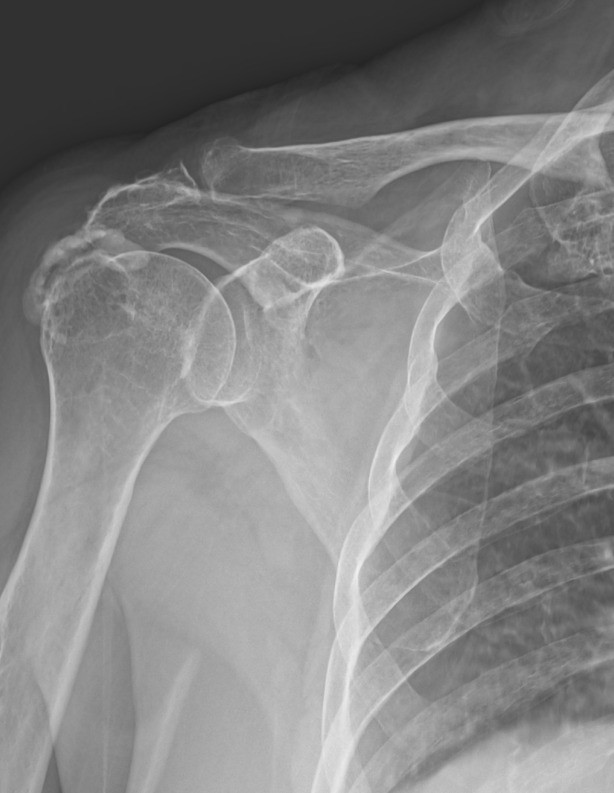

右肩痛1年 震波治療鈣化性肌腱炎獲改善

1名66歲婦人右肩斷斷續續疼痛近1年,近2週疼痛加劇,連梳頭、拿東西都相當困難,曾到他院就醫並被建議接受手術治療。後轉至營新醫院骨科求診,檢查發現是常見於中高齡族群的「鈣...…